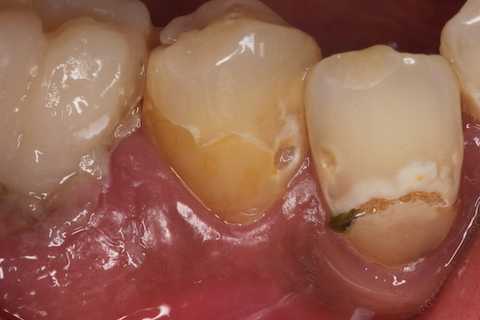

残根上のCR8 2025.10.28